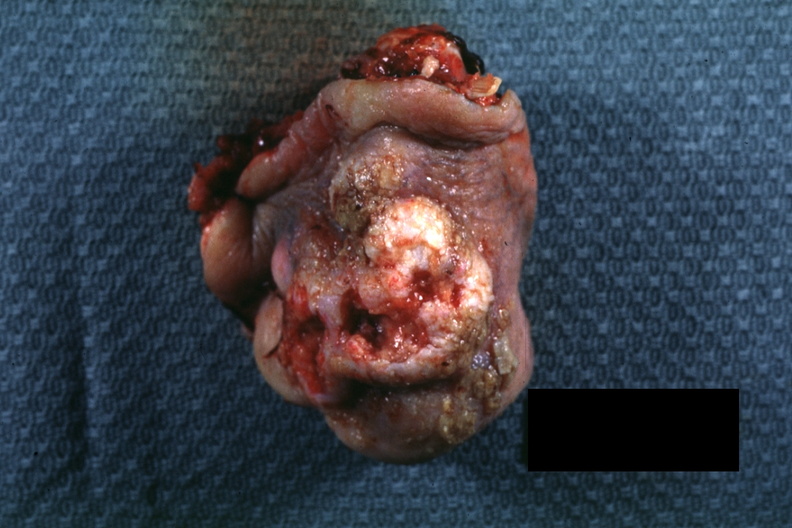

GROSS: SKIN: Squamous Cell Carcinoma: Gross portion of nose typical exophytic lesion with heaped-up margins and central ulceration

- gross, skin, squamous cell carcinoma